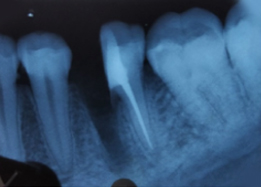

Hemisectomy

Pre-OP IOPAR